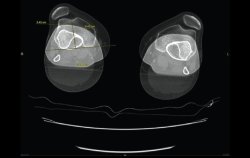

5. Mediciones

5.1. TA-GT (tuberosidad tibial anterior-garganta de la tróclea)

En pacientes sintomáticos con inestabilidad rotuliana, la TAC es útil para medir la TA-GT(10). La distancia TA-TG es una medida radiológica propuesta por Goutallier y Bernageau que sirve para cuantificar el ángulo Q. Consiste en medir la distancia en milímetros de la tuberosidad tibial anterior a la garganta de la tróclea proyectadas sobre una línea que pasa por los bordes posteriores de ambos cóndilos femorales, superponiendo 2 cortes axiales de TAC. Es una medida fiable y reproducible pero poco precisa, con un margen de error de más de 4 mm. La distancia TA-GT es mayor de 20 mm en el 56% de las inestabilidades rotulianas y tan solo en el 3% de la población sana(11)(Figura 28).

Figura 28. Corte axial de tomografía axial computarizada con superposición de imágenes con rótula y parte posterior de cóndilos y tuberosidad tibial anterior, que nos permite medir la distancia TA-GT, en condiciones normales hasta 2 cm.

5.2. Balance rotuliano

Mide la inclinación de la rótula en relación con el borde posterior de los cóndilos femorales (Figura 29).

Figura 29. Corte axial de tomografía axial computarizada con superposición de imágenes con rótula y parte posterior de cóndilos y tuberosidad tibial anterior, que nos permite medir el tilt o balance rotuliano, en condiciones normales hasta 20°.